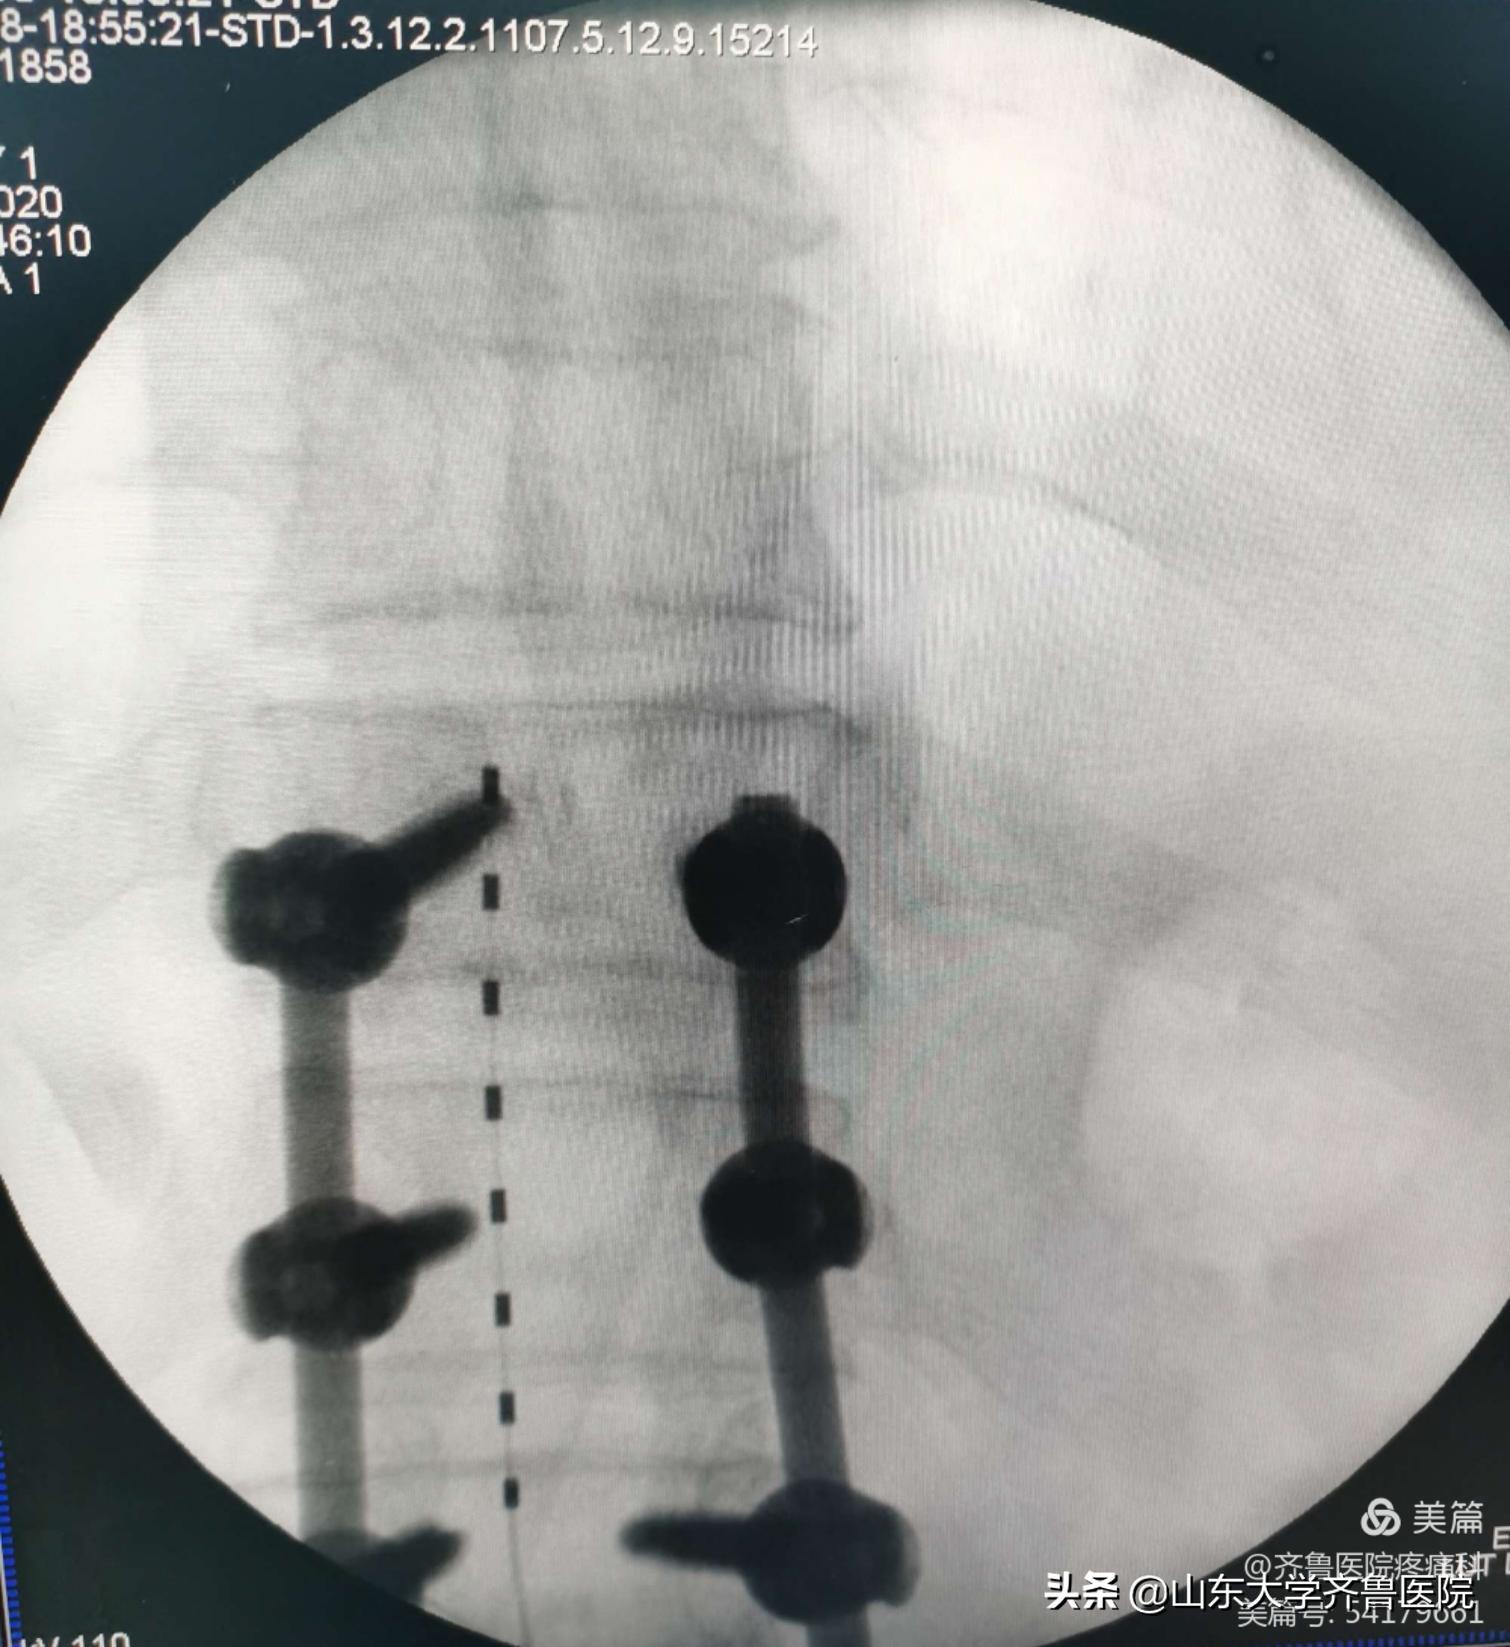

病例3 患者老年男性,72岁,因“双侧腰骶部及下肢疼痛3个月,加重1个月”以“腰椎术后顽固性疼痛”收入院。入院VAS评分7-10分。患者应用“塞来昔布、氨酚可待因、曲马多”等止痛药物效果差。术前评估后,患者在局麻下行脊髓电刺激器植入术,植入针状电极及临时刺激器。术中开机程控,患者感疼痛减轻,VAS评分2分,停用口服镇痛药物,经程控调整,VAS评分稳定至0-3分。7天后行永久脊髓电刺激器植入术,患者VAS评分稳定于0-2分,未出现术后不良反应及并发症。

图4.腰椎术后顽固性疼痛患者术后X线检查电极位置良好